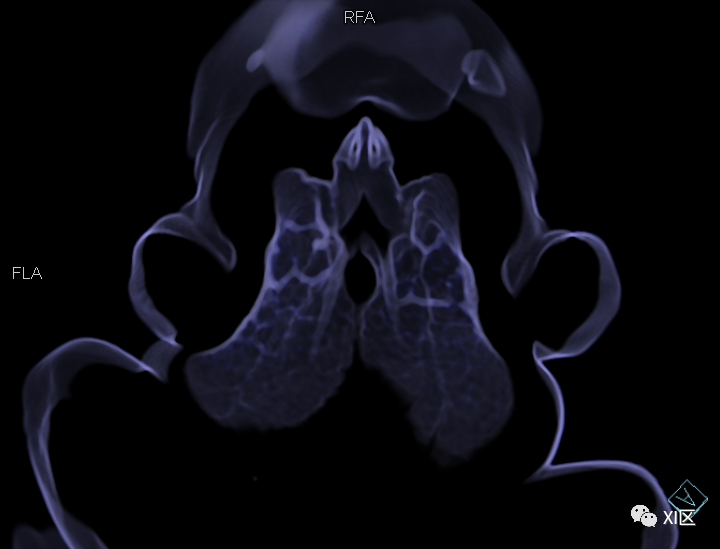

先来欣赏一下三维重建的效果

牛蛙的三维重建

牛蛙的三维重建,显示牛蛙肉、肺和骨骼